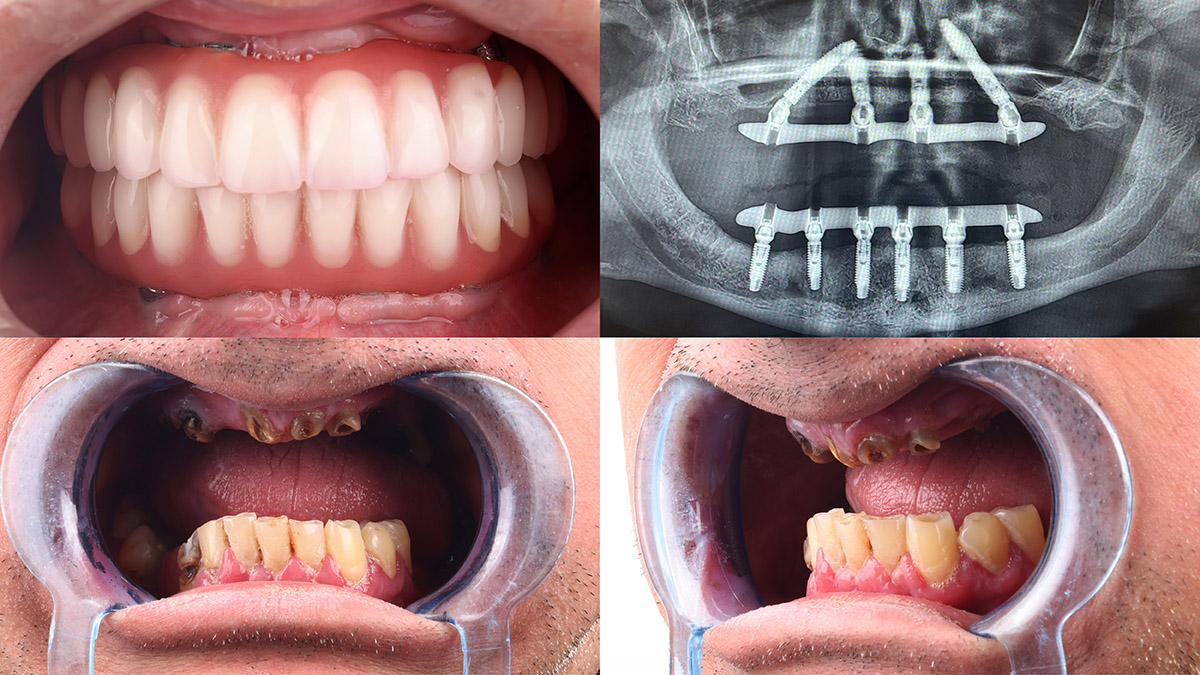

All

on 6

Pacijentkinji je urađena implantološko-protetska terapija metodom All-on-6 u gornjoj i u donjoj vilici. Kao konačno rešenje postavljen je fiksni cirkonijumski (zircon) most.